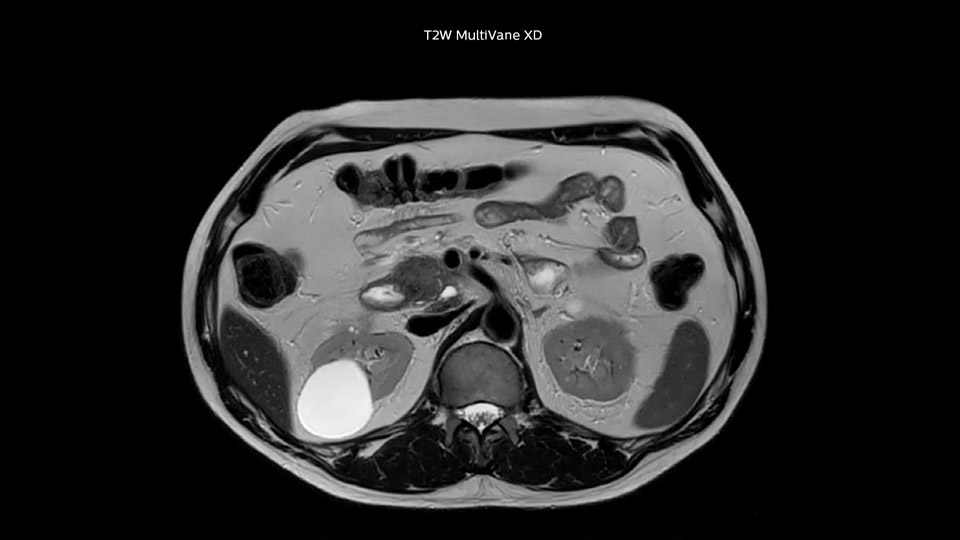

Dr. Baumann then implemented MultiVane XD for motion correction. It uses an extended reconstruction algorithm for imaging that is virtually motion free. “With MultiVane XD we get excellent motion-corrected images with high spatial resolution. We typically first optimize our scan for high image quality, and when satisfied with that, we try to reduce the scan time. So, we combined MultiVane XD with dS SENSE, which allows us to shorten the scan time,” he explains. “The performance of MultiVane XD in liver imaging is outstanding. MultiVane XD with dS SENSE is a powerful development in improving liver image quality.” “As we use breathhold imaging for T2-weighted liver scans, we depend on the patient’s ability to cooperate with the exam. This can present a real challenge when we are looking for small lesions, such as in our oncological patients. However, with MultiVane XD motion correction, we get excellent images. This is important for our surgeons, because they want to know exactly where the lesions are.”

In this example the image quality of the MultiVane XD images is evidently better than in the images without MultiVane XD. Ingenia 1.5T with dS Torso coil solution.

“Our liver exams are quite fast,” says Dr. Baumann. “If the patient tolerates it, we use an arms-up position to reduce the FOV and speed up the exam with dS SENSE.” “We acquire one transversal high resolution T2-weighted sequence with 3 mm slice thickness, for example for pancreas or liver lesions. Then we also add a T2 fat suppressed MultiVane XD SPIR sequence. We perform these two routinely in our liver imaging. We use high dS SENSE factors to significantly shorten scan times to 2-4 minutes, which can improve our protocol; it’s a very robust scan.” “We include mDIXON for the dynamic sequences because of the robust and homogeneous fat suppression we get with that. We had been using eTHRIVE, but we are now quite happy with mDIXON. Sometimes we use a medication to calm the bowels, to further improve the image quality.”